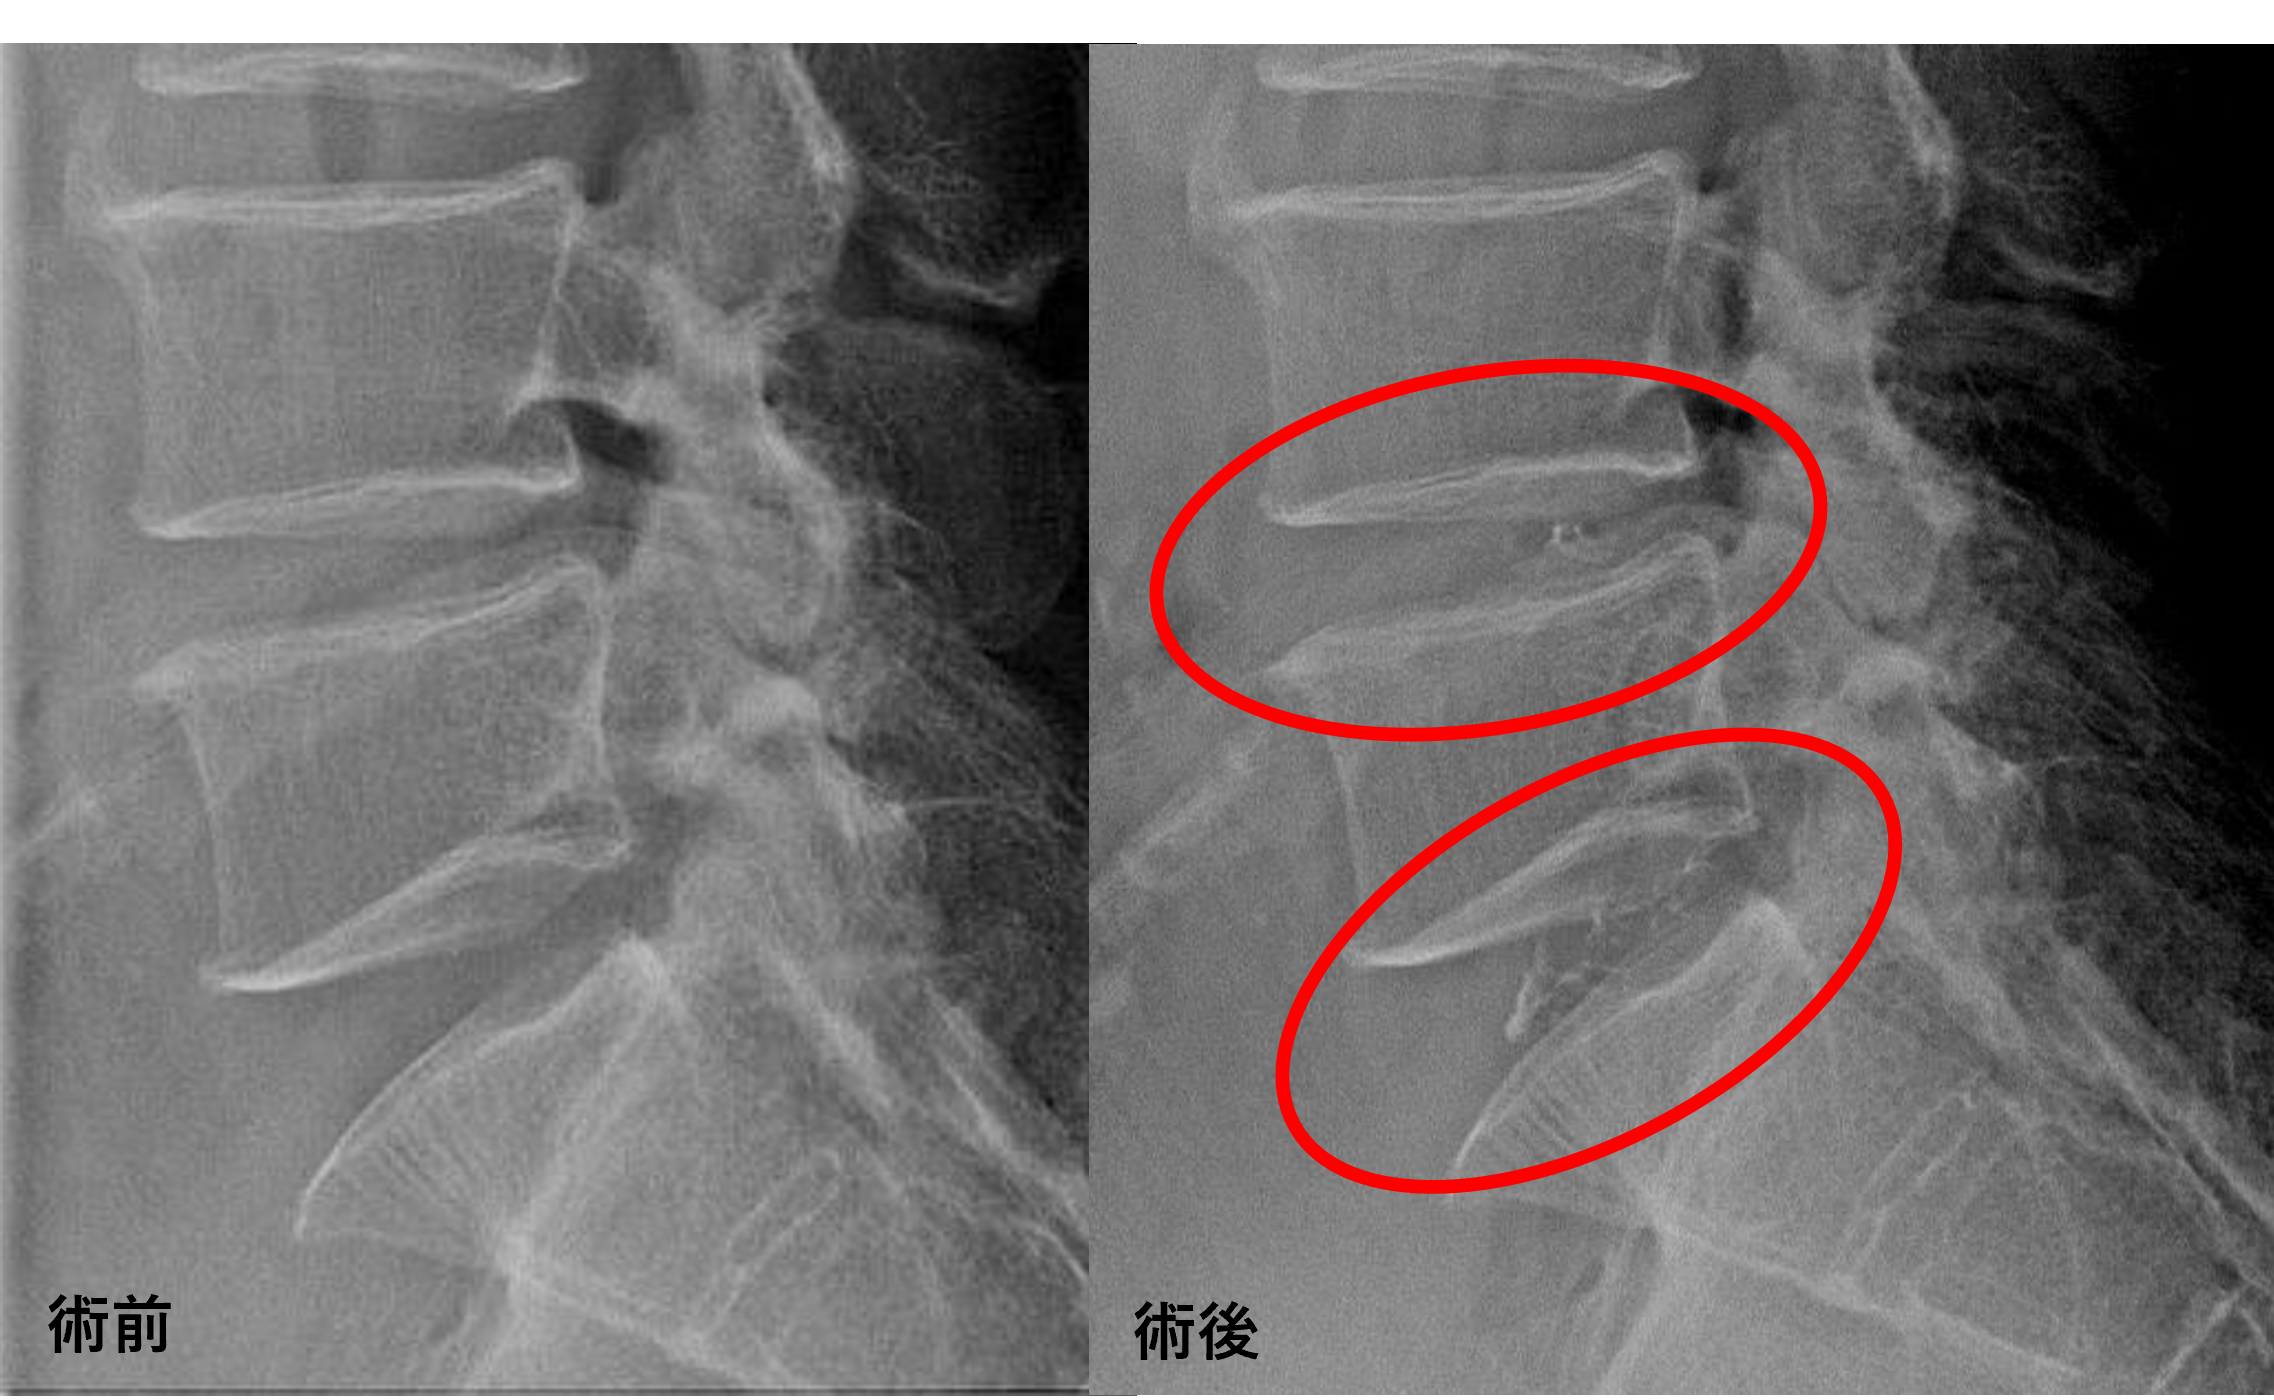

画像及び所見について

- L4/5、5/s – 椎間板変性、膨隆

以上のことが画像上認められました。

L4/5、5/sの椎間板所見による脊柱管の圧排が、症状の原因の可能性が高い。

患者様と相談の元、L4/5、5/sにセルゲル法を施行